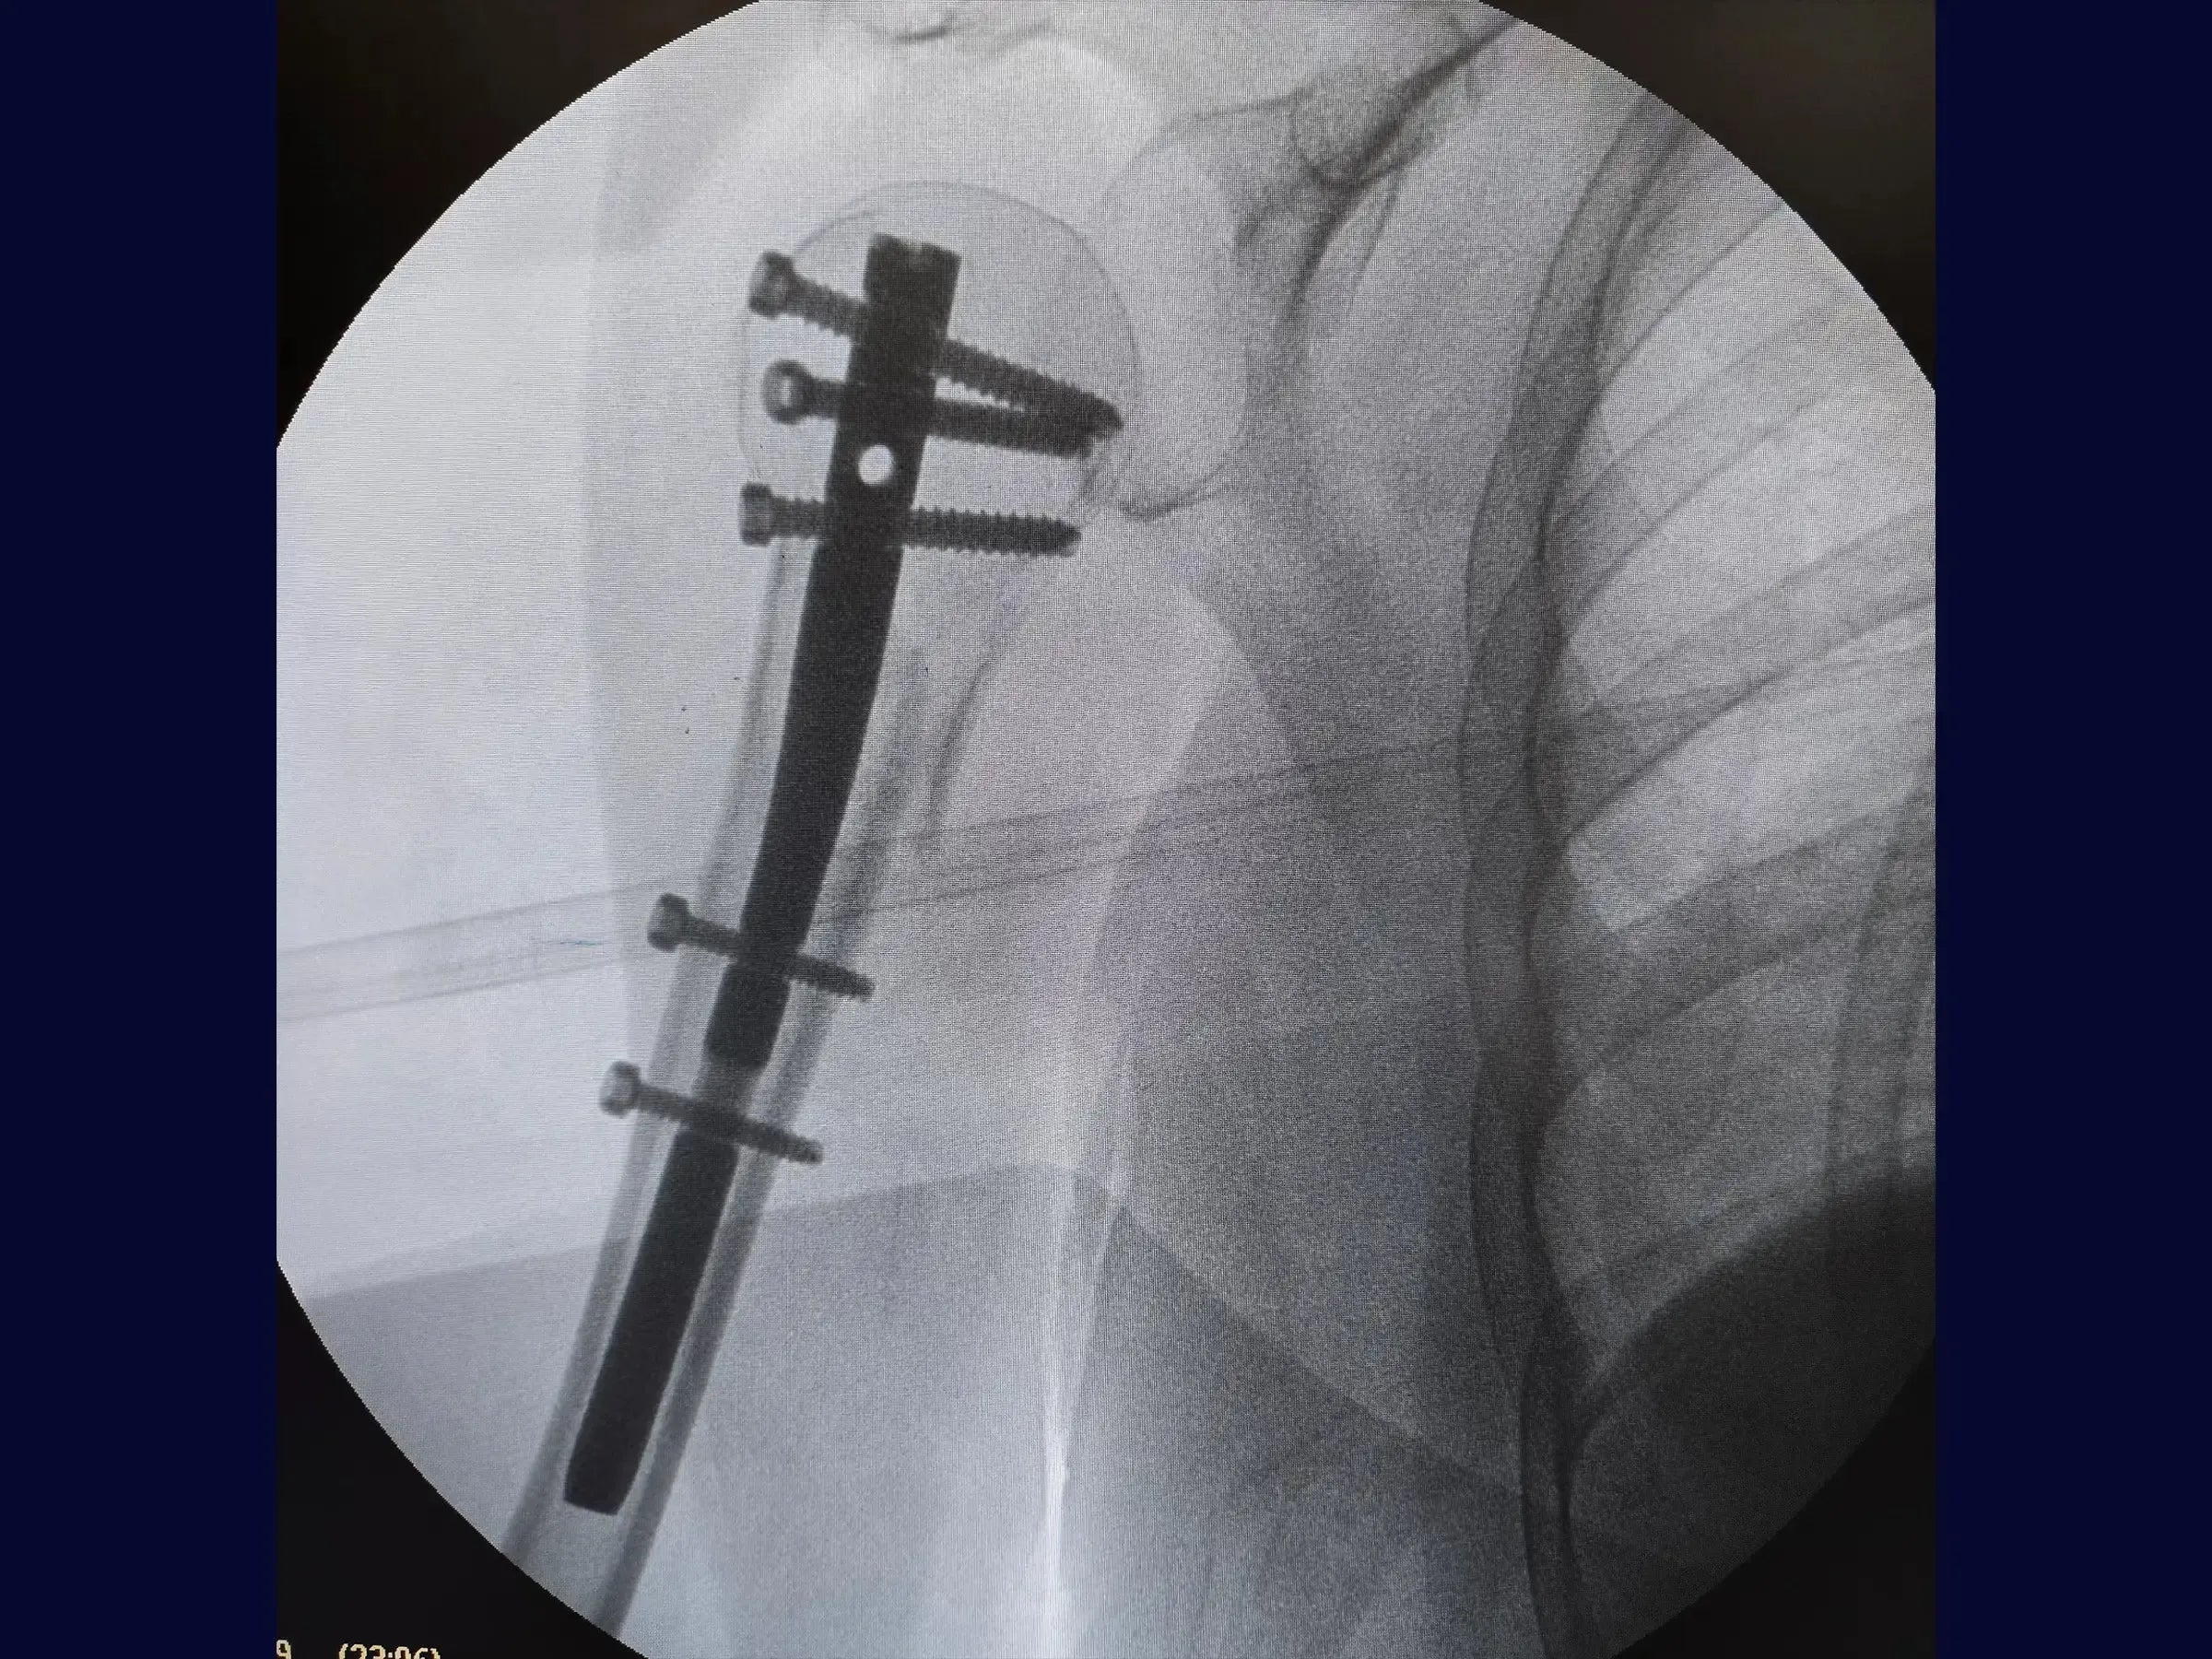

- Non-Cannulated Rod Insertion Technique: Step-by-step approach for opening the medullary canal and manual introduction of the rod under fluoroscopic control.

- Systematized Percutaneous Blocking: Protocols for safe and effective insertion of proximal and distal locking screws.

- Prevention of Complications at Finalization: Strategies for guide removal and introduction of the plug screw, minimizing complications and the need for access enlargement.